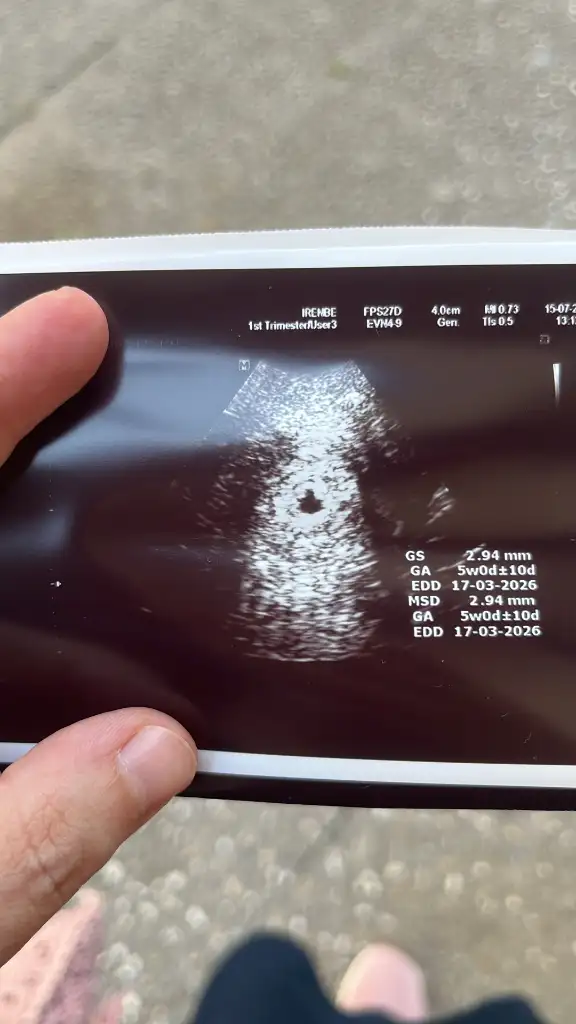

Transfer tarihim 23 haziran. 5+4 haftalığım ve ultrason 5+0 görünüyor. Kese boyutu da bana küçük gibi geldi. Doktor ne olumlu ne olumsuz konuştu sanki arada kalmış gibiydi. 10 gün sonraya tekrar çağırdı. Yorum yapabilecek olan var mı?

Evet o problem değil sanki ama mm olarak haftama göre sanki kese küçük gibi. Okuduğum kadarıyla 5 mm civarlarında oluyormuş bu haftada. O yüzden içime kurt düştü